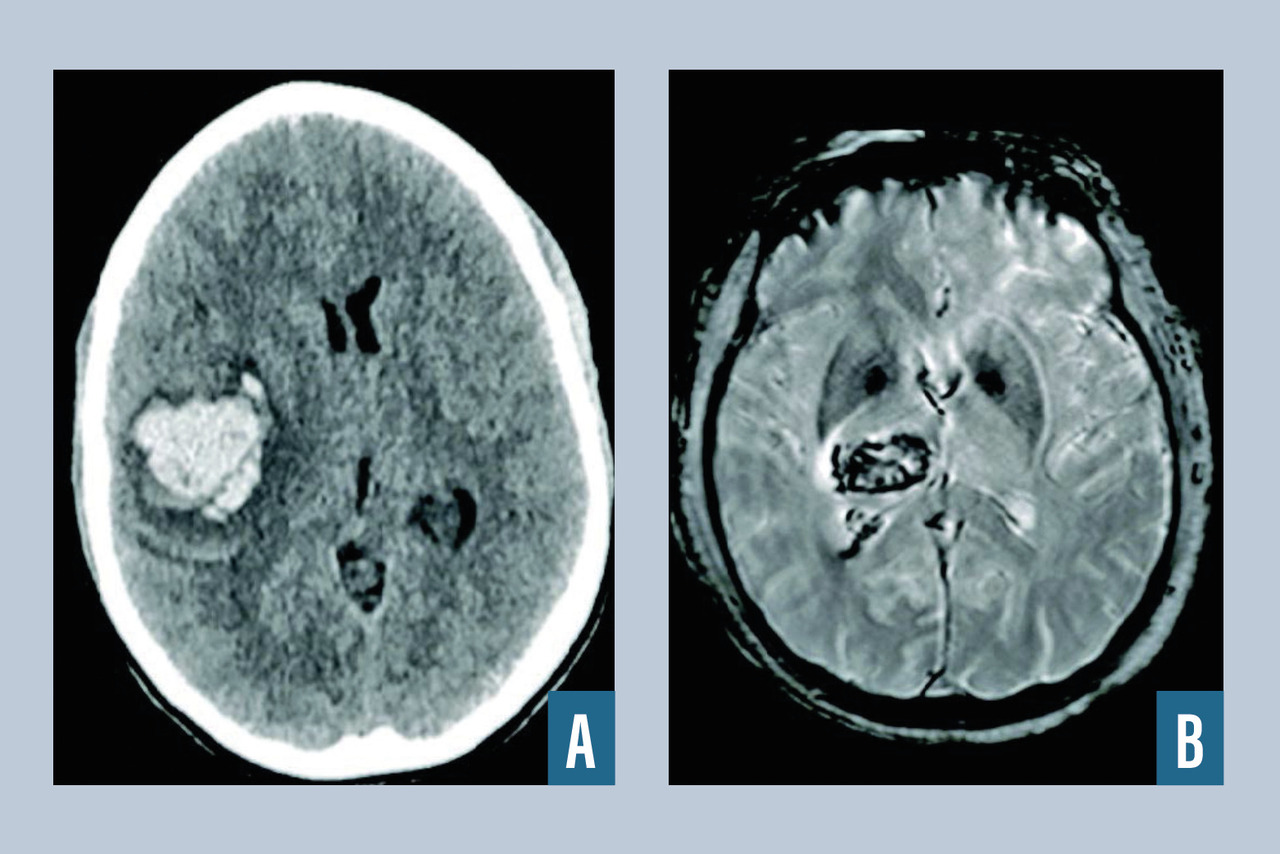

L’infarctus cérébral (fig. 1 ) correspond à un foyer circonscrit de nécrose ischémique due à l’interruption brutale de l’apport sanguin artériel par occlusion d’une artère cérébrale ou à destination cérébrale. On distingue deux types de mécanisme : l’occlusion thromboembolique (embolie du système artériel, embolie cardiaque, thrombose artérielle in situ) ou, plus rarement, des phénomènes hémodynamiques de bas débit cérébral (sur une sténose, sur un arrêt cardiaque en peropératoire). On dispose de traitement de recanalisation (chimique [thrombolyse intraveineuse] et mécanique [thrombectomie mécanique]) à fenêtre thérapeutique étroite, et d’autant plus efficace que réalisé le plus tôt possible par rapport à l’apparition des symptômes, nécessitant une prise en charge dans des filières organisées autour des unités neurovasculaires (v. Focus sur les filières de prise en charge et la thrombolyse). En effet, depuis 2004, on peut avoir recours à la fibrinolyse par rt-PA dans les infarctus cérébraux de moins de vingt-quatre heures. En 2015, les sociétes savantes neurovasculaire et de neuroradiologie ont validé le recours à la thrombectomie mécanique avec (thrombolyse combinée) ou sans (thrombectomie mécanique seule) thrombolyse intraveineuse dans les infarctus cérébraux secondaires à une occlusion proximale (carotide interne intracrânienne, artère cérébrale moyenne portion M1 et M2 proximale) dans les six heures puis dans les vingt-quatre heures suivant le début des symptômes pour certains patients sélectionnés par l’IRM de perfusion. La prise en charge des accidents vasculaires cérébraux à la phase précoce a fait l’objet de recommandations de la HAS en 2009 et les sociétés savantes (SFNV, ESO) mettent régulièrement à jour les recommandations sur la prise en charge de l'AVC à la phase aiguë et en prévention secondaire. L’IRM cérébrale avec séquences de diffusion, FLAIR, T2* et ARM-TOF est l’examen de référence pour le diagnostic d’infarctus cérébral récent (hypersignal en diffusion, qui devient visible après 4 à 6 heures en FLAIR), d’occlusion artérielle (ARM-TOF). Elle permet également d’éliminer une hémorragie (T2*). Le recours à l’IRM de perfusion permet de sélectionner, via un logiciel de lecture automatisé, les patients pouvant bénéficier d’une thrombectomie mécanique entre six et vingt-quatre heures après le début des symptômes. Les causes des infarctus cérébraux sont dans 30 % des cas athérothrombotiques, dans 20 % cardio-emboliques (fibrillation atriale), dans 20 % d’origine lacunaire dans le cadre d’une maladie des petites artères. Dans 25 % des cas, la cause reste indéterminée à l’issue du bilan.

L’hématome intracérébral est une collection de sang consécutive à la rupture d’un vaisseau intracrânien (fig. 2 ). L’hypertension artérielle est la première cause, et l’hémorragie est alors très souvent localisée au niveau des noyaux gris centraux. Lorsque l’hémorragie est située en superficie, elle est dite lobaire, et après 50 ans, le diagnostic d’angiopathie amyloïde est fréquemment rencontré après exclusion des autres diagnostics (tumeurs, traumatisme…). Une autre cause est la rupture d’une malformation vasculaire, que ce soit une malformation artérioveineuse, un anévrisme ou un cavernome. Parmi les autres causes, on cite la thrombophlébite cérébrale et les troubles de la coagulation spontanés ou iatrogènes (traitements antithrombotiques). Le scanner cérébral, qui est l’examen de référence en cas d’hémorragie cérébrale, met en évidence une plage en hyperdensité et est le plus souvent complété par un scanner cérébral avec injection et un angioscanner cérébral à visée étiologique (recherche de tumeur, de malformation vasculaire, de thrombose veineuse cérébrale). L’IRM cérébrale avec ARM peut être intéressante lorsque le scanner n’est pas contributif pour rechercher une cause de l’hémorragie (stigmates de maladies des petites artères liées à l'âge et à l'hypertension artérielle, angiopathie amyloïde, tumeur cérébrale). En l’absence de cause retrouvée à la phase aiguë, l’IRM cérébrale injectée doit être réitérée à trois mois pour s’assurer de l’absence de lésion sous-jacente. Le recours à l’artériographie cérébrale est fréquent dans le cadre du bilan étiologique de l’hématome du sujet jeune, en l’absence de cause évidente.